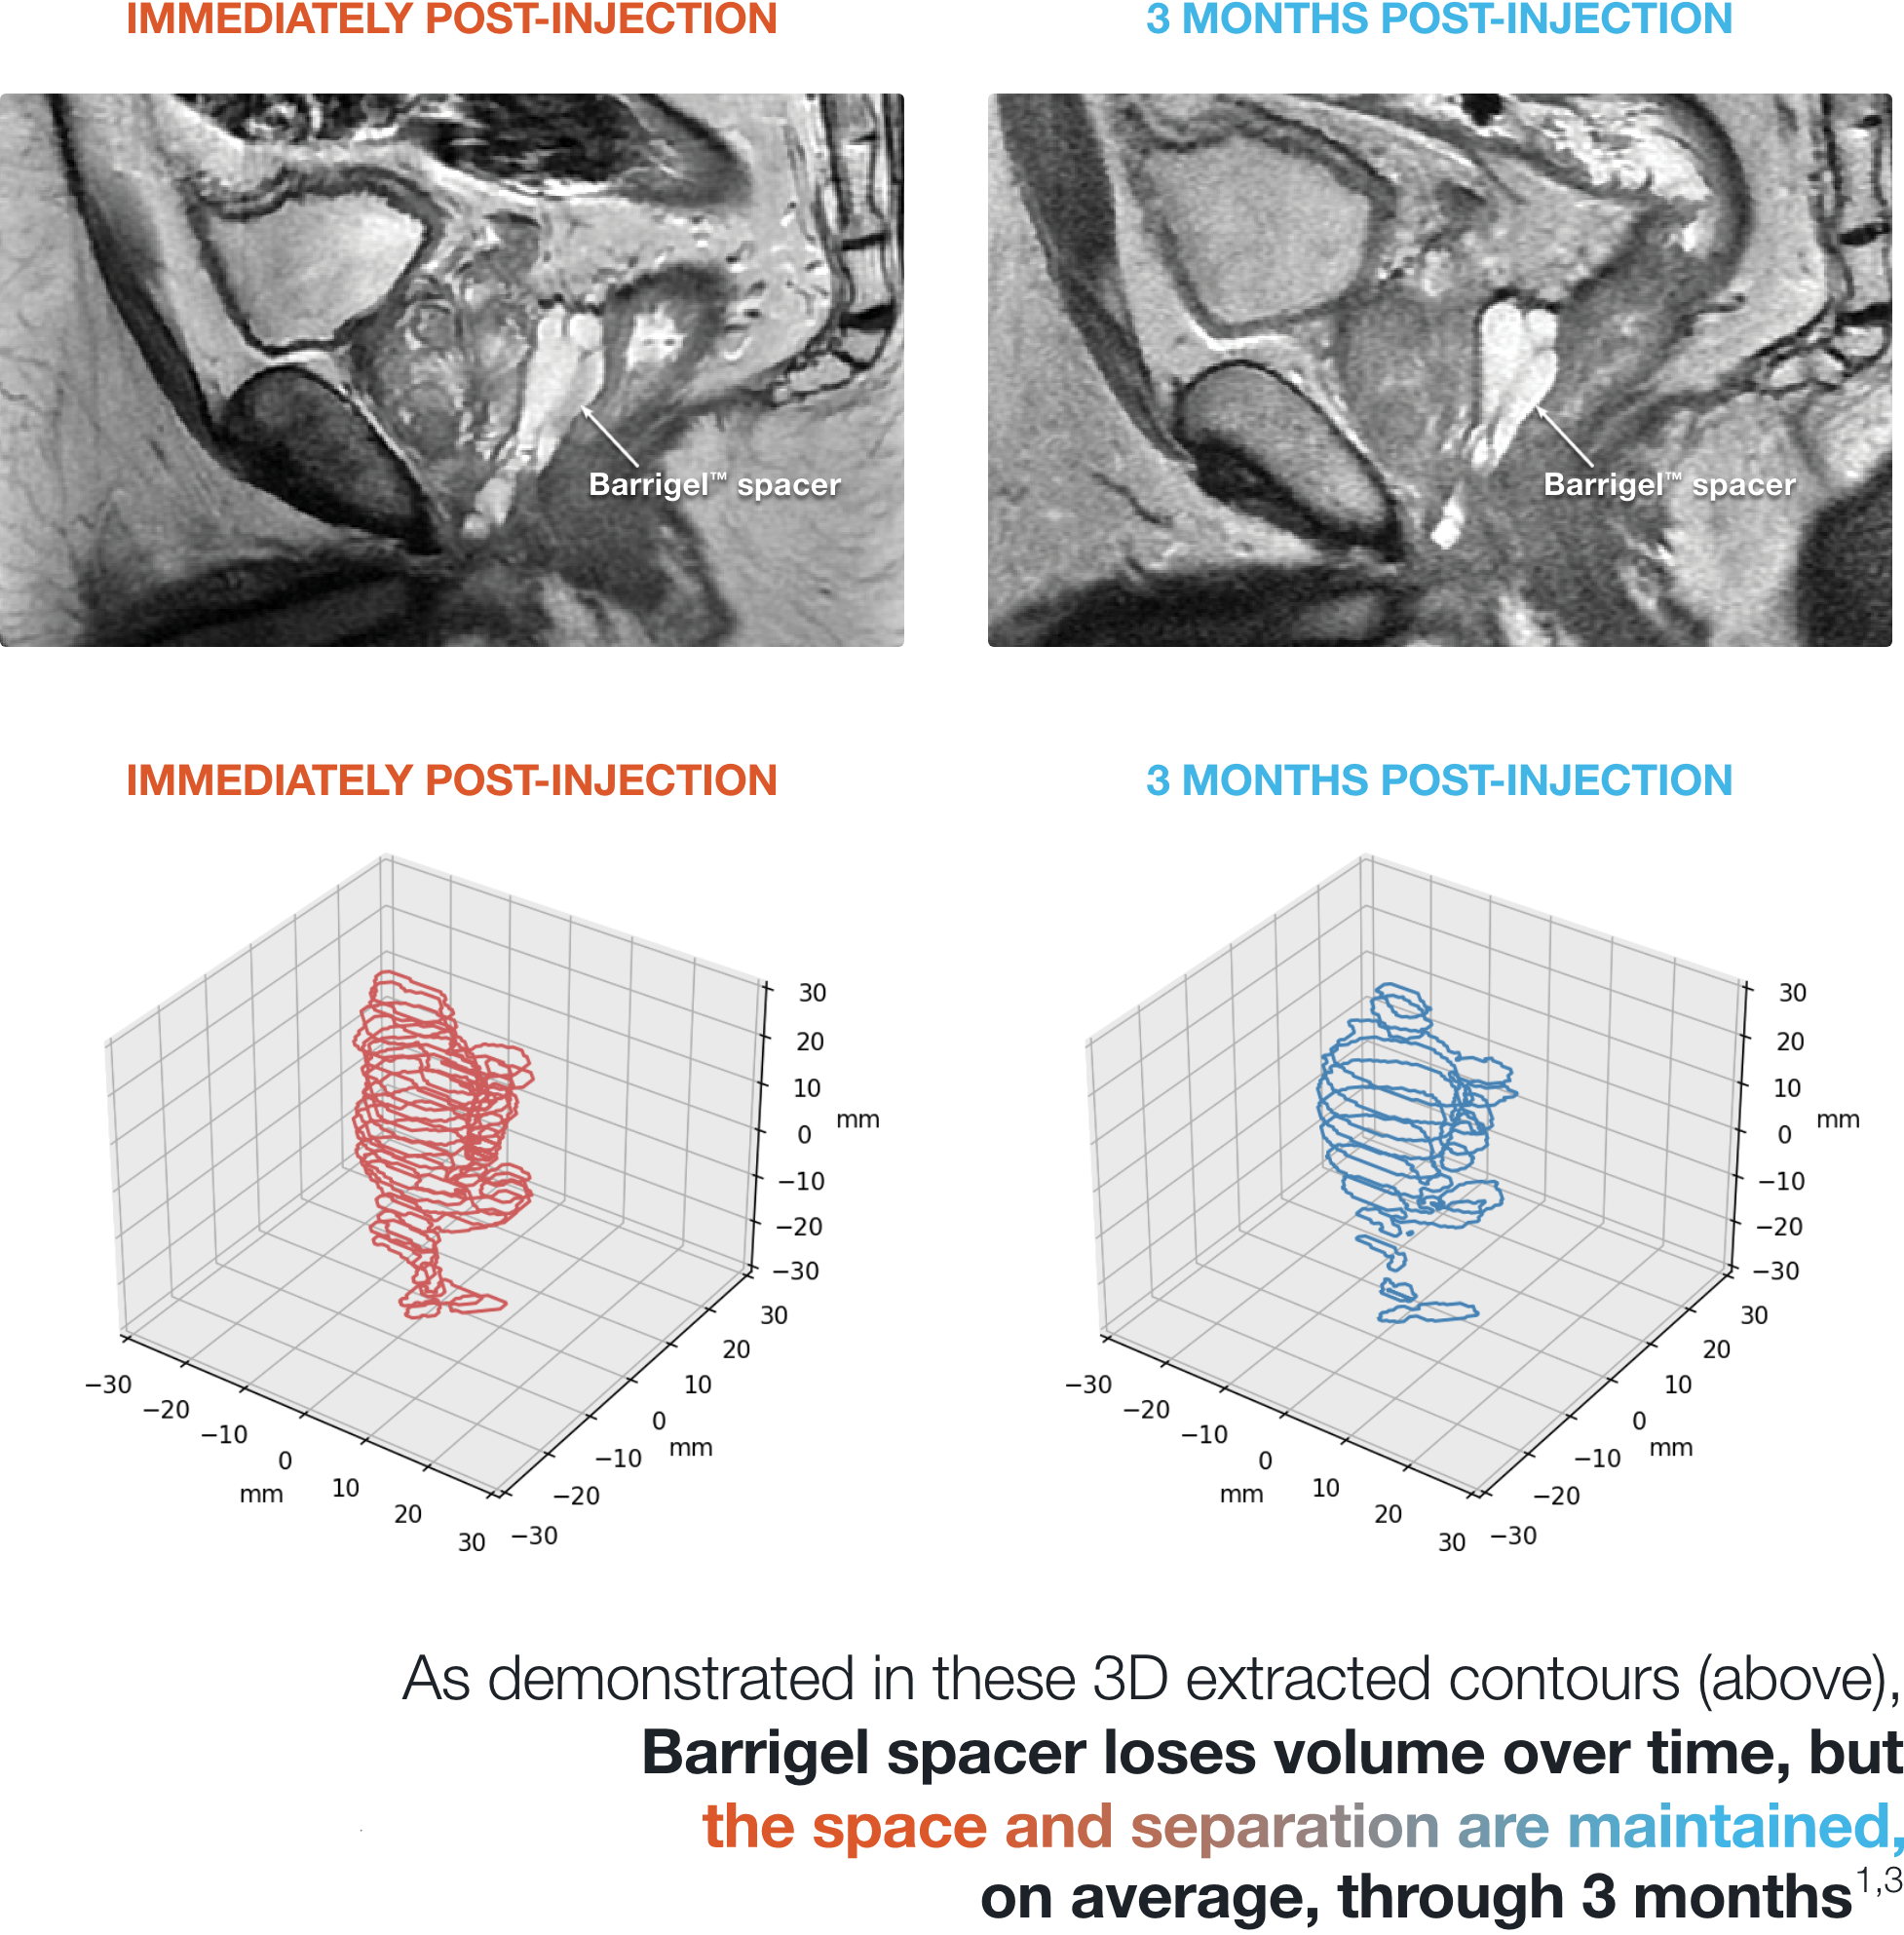

PATIENT EXAMPLE SHOWING

STABLE SEPARATION DURING RESORPTION

Results may vary.

MEAN PROSTATE-RECTUM SEPARATION (DIMENSIONAL STABILITY)